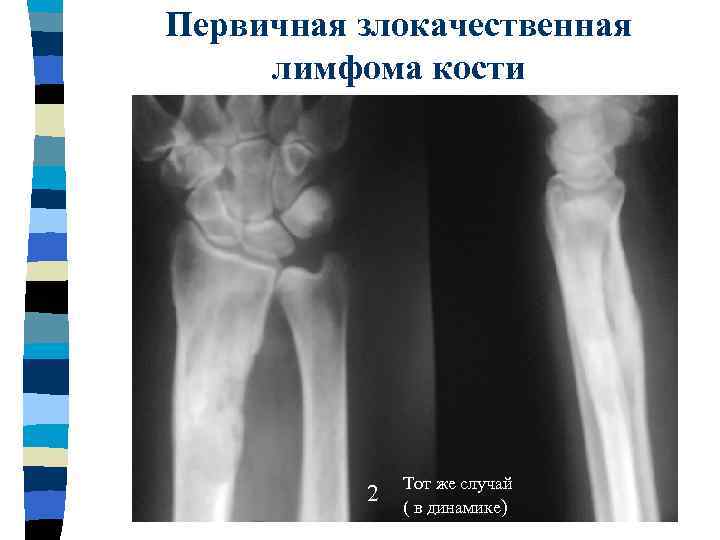

Первичная злокачественная лимфома кости В области метадиафиза луча определяется участок измененной структуры с наличием мелких очагов деструкции и периостальные наслоения

Первичная злокачественная лимфома кости 2 Тот же случай ( в динамике)

Первичная злокачественная лимфома кости 3 4 Подобные изменения костной ткани определяются в области средней трети левой м/берцовой кости (в динамике)